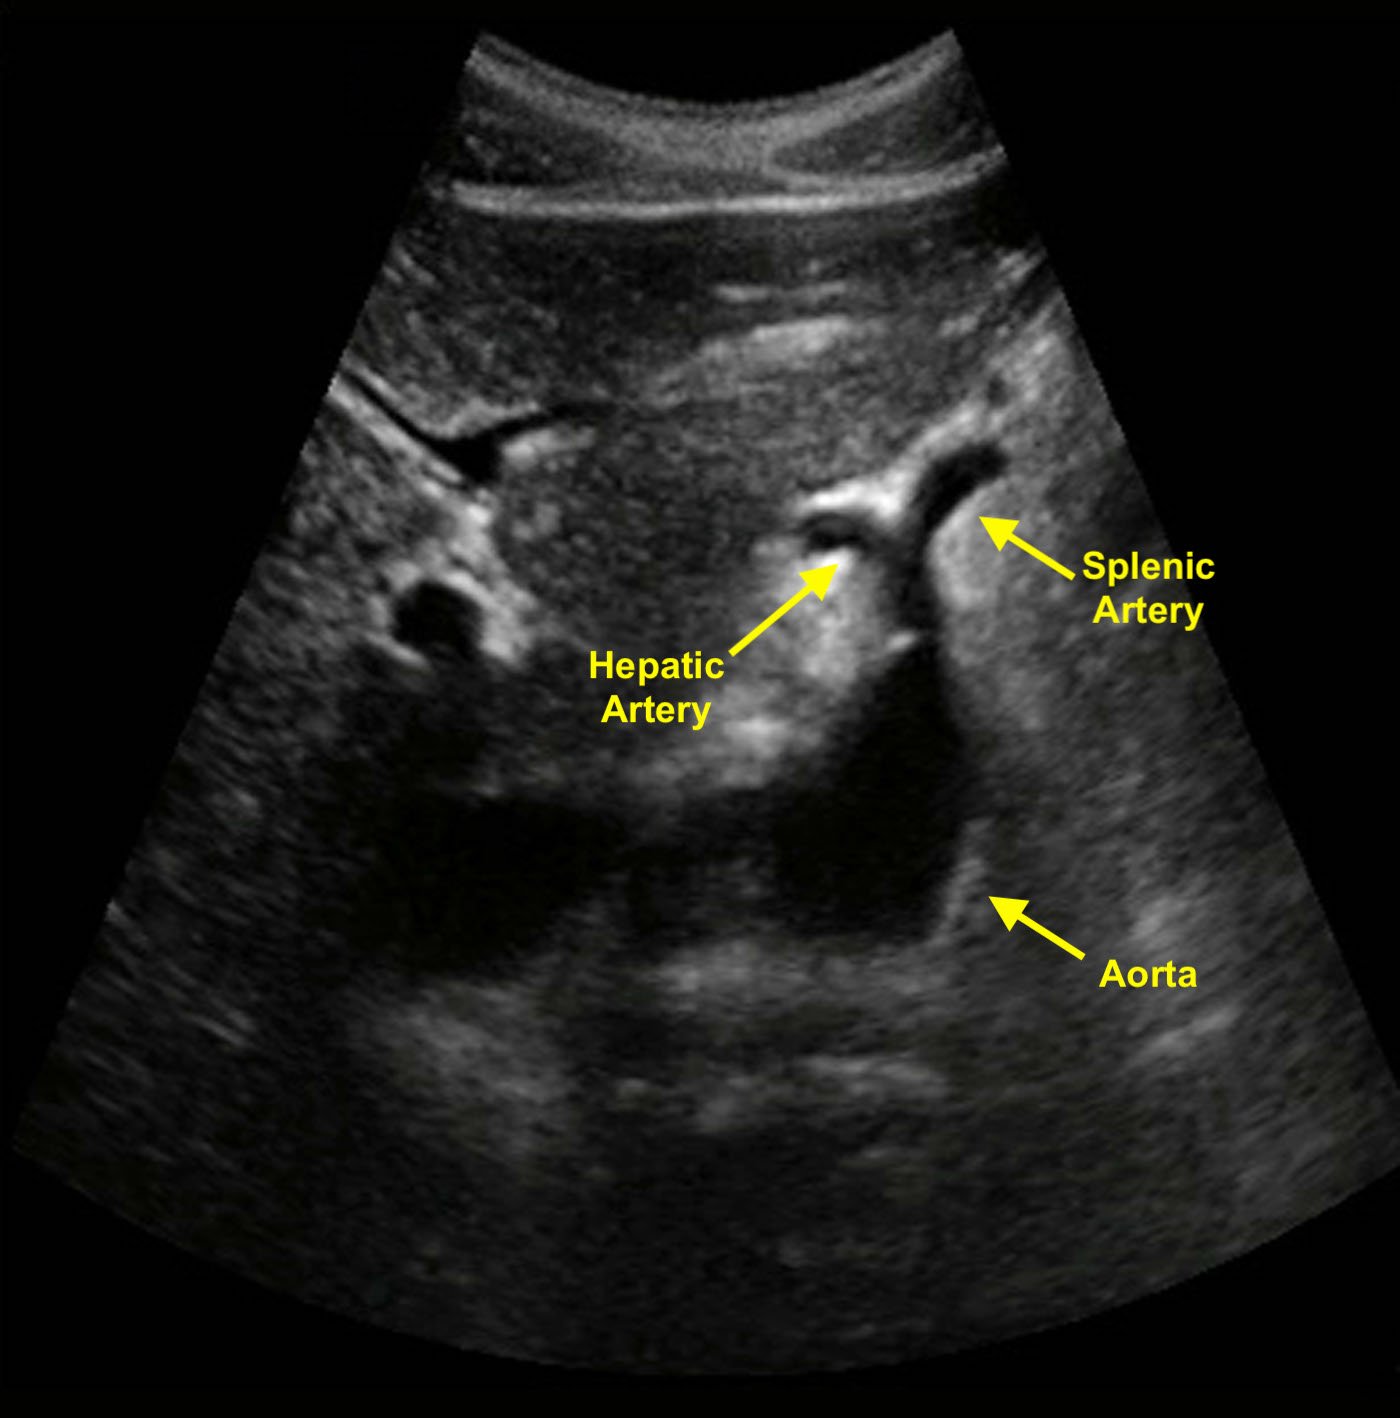

- Celiac trunk is first major vessel to arise from the abdominal aorta in the midline anteriorly (Figure 1). This short vessel can often be seen in the transverse plane, dividing in a “wide Y.” This sonographic view is known as the “seagull sign.”

- Fork on patient’s right is common hepatic artery.

- Fork on patient’s left is splenic artery.

- Figure 1. Transverse image of the aorta shows a classic example of the seagull sign. The celiac trunk branches into the hepatic and splenic arteries.